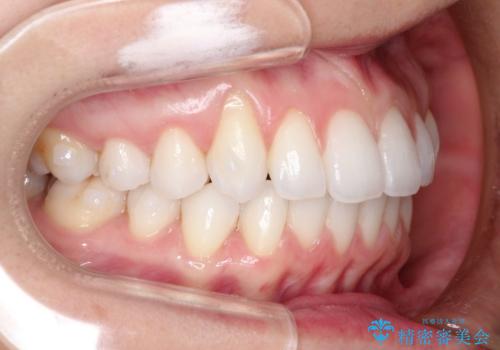

- 主訴:「右上犬歯を引っ込めて、歯並びをキレイにしたい」

右上の八重歯を気にされてご来院されました。結婚式を控えていたため挙式にまでに可能な限りキレイにしたいとのことでした。

右上の犬歯の歯茎は矯正前から退縮を起こしていましたが、矯正後もその退縮に関しては変化がありませんでした。今回は患者様が歯肉退縮に関しては治療をご希望ではありませんでしたが、当院ではこのように歯茎が下がり露出した根面を、歯茎を移植することでカバーし見た目を改善する手術を行っています。